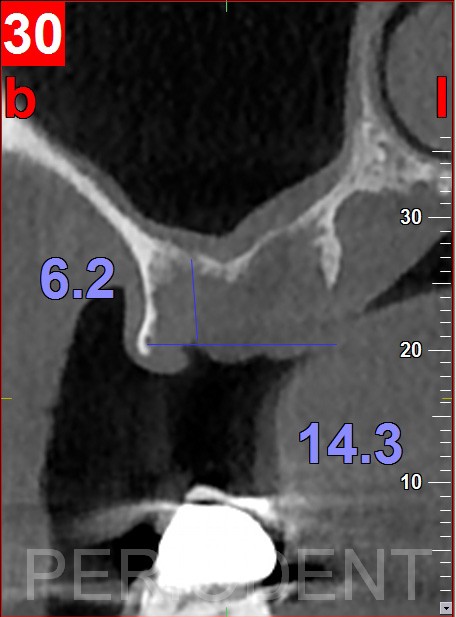

患者決定採用植牙治療,口內照根尖片及CT檢查結果

一個月後進行第二大臼齒遠心手術及第一大臼齒補骨手術